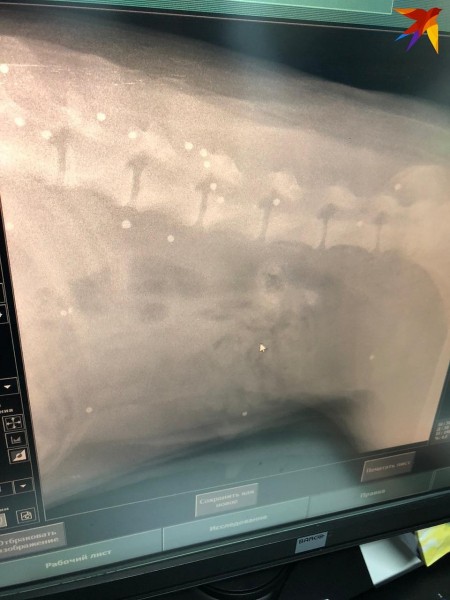

— Взяли анализы — показатели не завышены, сделала УЗИ — внутренние органы целы. Тогда решили отвезти на рентген, — продолжает Наталья Федосеева. — Тело собаки буквально изрешетили — металлическая дробь, кажется, была повсюду — в грудной клетке, в брюшной полости, в районе позвоночника. Сколько раз в нее стреляли, сказать сложно. Мы начали считать все пули, когда цифра перевалила за (!) 100, мы сбились!

Собаке сделали ренгтен и обнаружили 100 пуль Видео: instagram.com/natali_vetdoc.

— Так как дробь сделана, скорее всего, из свинца, может начаться отравление тяжелыми металлами. Ко всему прочему мы не можем провести диагностику МРТ, так как пули будут «выстреливать» из тела из-за волнового биополя, — объясняет врач. — Конечно, необходимо извлечь хотя бы часть пуль, но мы понимаем, что все их вытащить будет просто невозможно — собака может умереть.